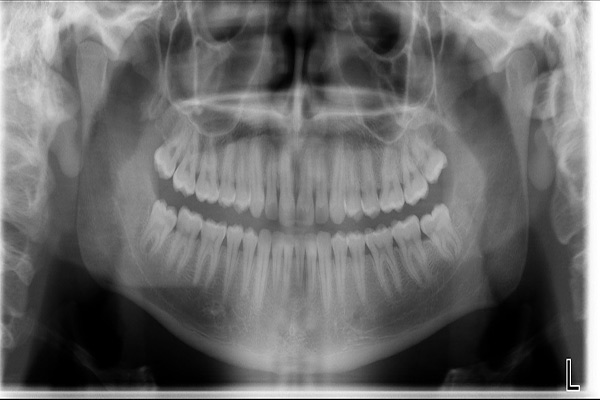

دندانپزشک ابتدا عکس پرتوی ایکس از دهان میگیرد تا بر اساس موقعیت دندان و ساختارهای پیرامون، برای بهترین روش درمانی برای کشیدن دندان تصمیم گیری نماید. سابقه پزشکی و دندانپزشکی خود را در اختیار دندانپزشک قرار دهید و فهرست کاملی از تمام داروهایی که مصرف میکنید بنویسید. منظور از داروها تمامی داروهای تجویزی و غیر تجویزی، گیاهان دارویی، ویتامینها و مکمل ها میباشد.

در صورتی که قصد دارید دندان عقل خود را بکشید ممکن است ابتدا عکس پرتوی ایکس پانورامیک گرفته شود.

درعکس پانورامیک یک عکس از تمامی دندانها گرفته میشود تا موارد زیر مشخص شود: